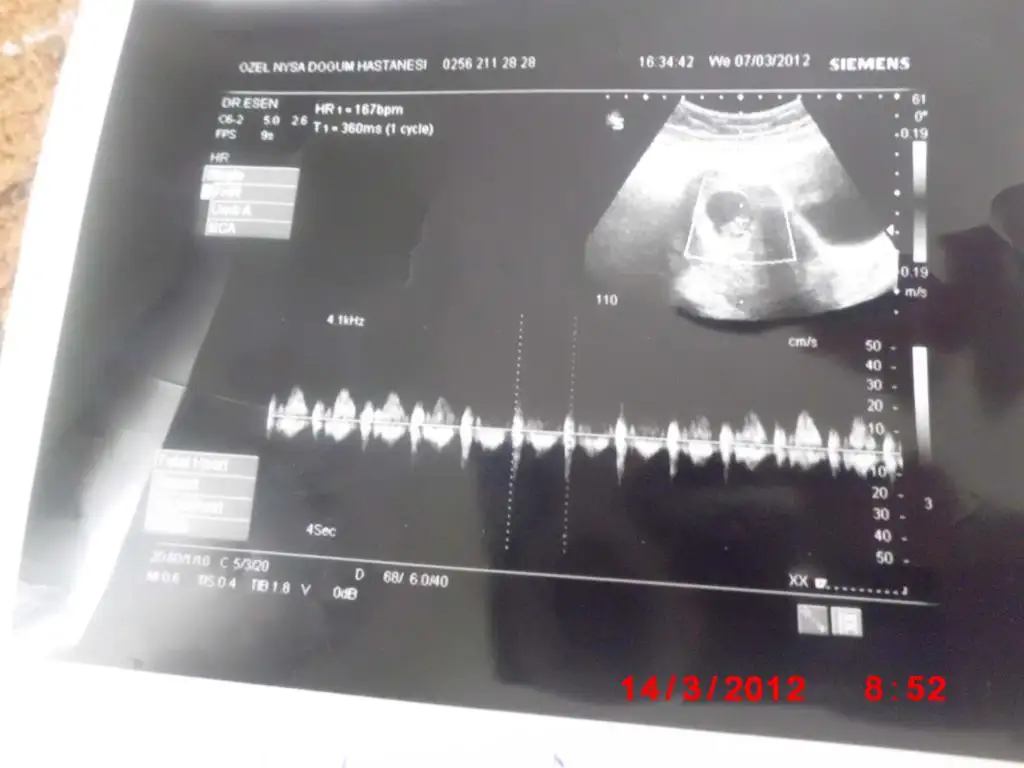

bugün sizlere bebişimin 8 haftalık ultrason resmini paylaşmak istedim

maşşalah bebişine canım

bahsettiğim teorye göre kızın olucak gibi görünüo

tabi ne kadar doğrudur bilemem

benm de kesenin sağına böyle yapışmıştı

ben de kız diorum

bakalım çıkıcak mı